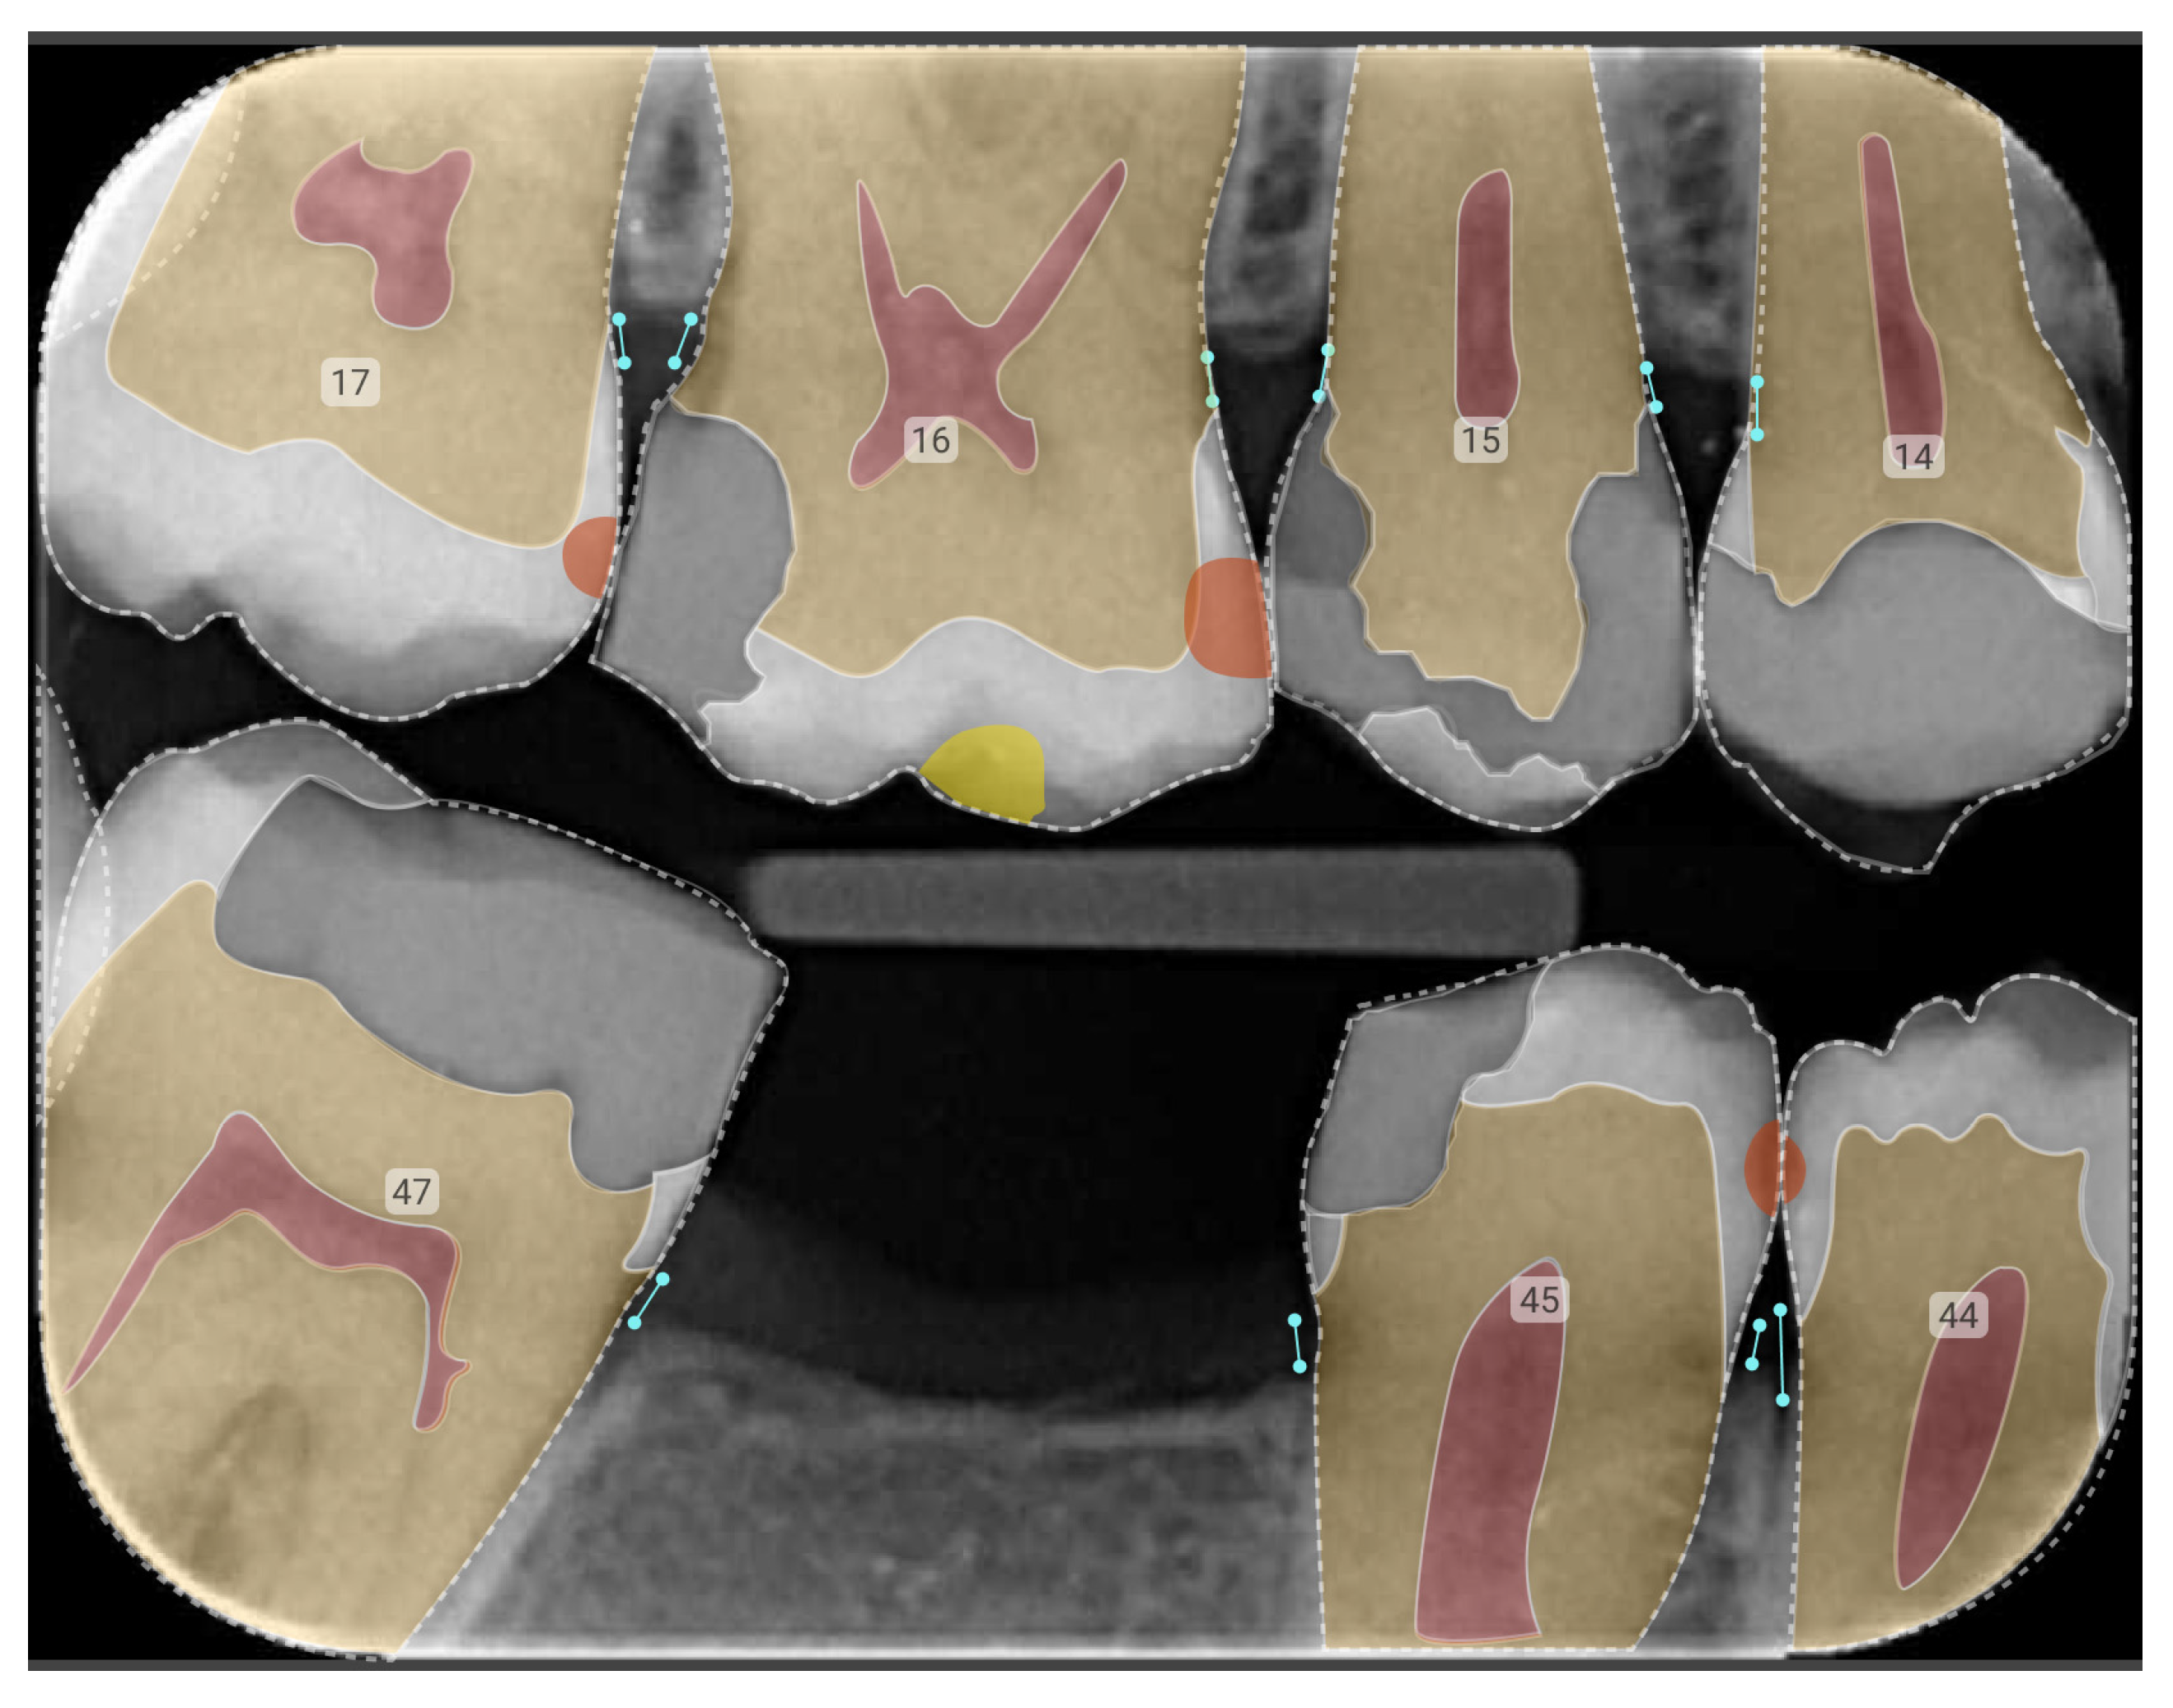

5. Case Study: AI-Powered Dental Caries Detection and Management

| Tooth, Surface | Detection Mode | Findings/OD | Treatment Plan (Procedure) | Item Code | Cost | Inference | |

|---|---|---|---|---|---|---|---|

| Dentist | 23 | Inspection | Initial caries | Adhesive restoration—anterior tooth—direct | 522 | $228.99 | Dentist false positive |

| 14 | Inspection | Moderate caries | Adhesive restoration—posterior tooth—direct | 533 | $286.01 | Dentist true positive | |

| CoTreat Navigator® | 36D 4 | PBW 1 | Initial Stage ICCMS RA 3 2 | Adhesive restoration—posterior tooth—direct | 532–535 | $244.53–$383.93 | Dentist false negative |

| 36B | Photo | Moderate caries ICDAS Code 3 3 | |||||

| 14DM | PBW 1 | Initial Stage ICCMS RA 3 2 | Adhesive restoration—posterior tooth—direct | 533–535 | $286.01–$383.93 | Dentist true positive | |

| 14B | Photo | Moderate caries ICDAS Code 3 3 |